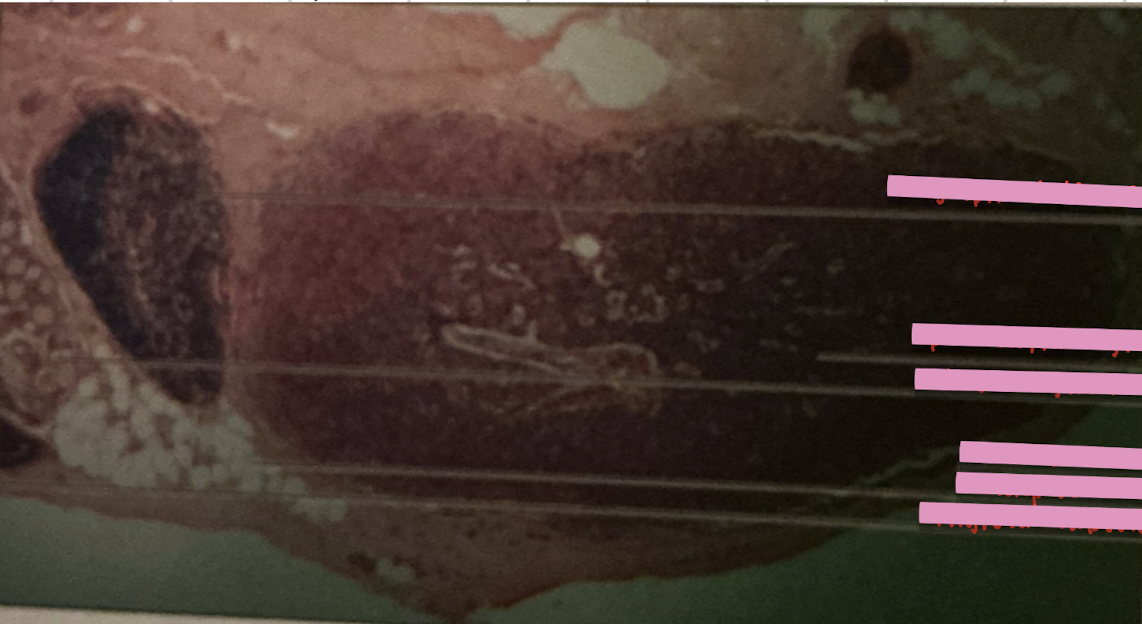

lympatic vessel valve

lymph node

retrograde flow

flow of lymph b/w nodes or organs relies on skeletal muscle and one-way valves to prevent __________

B cell mitosis

each lymph follicle w/in each lymph node is active center for ___________

dendritic cells

______________ capture antigens and bring them to lymph nodes